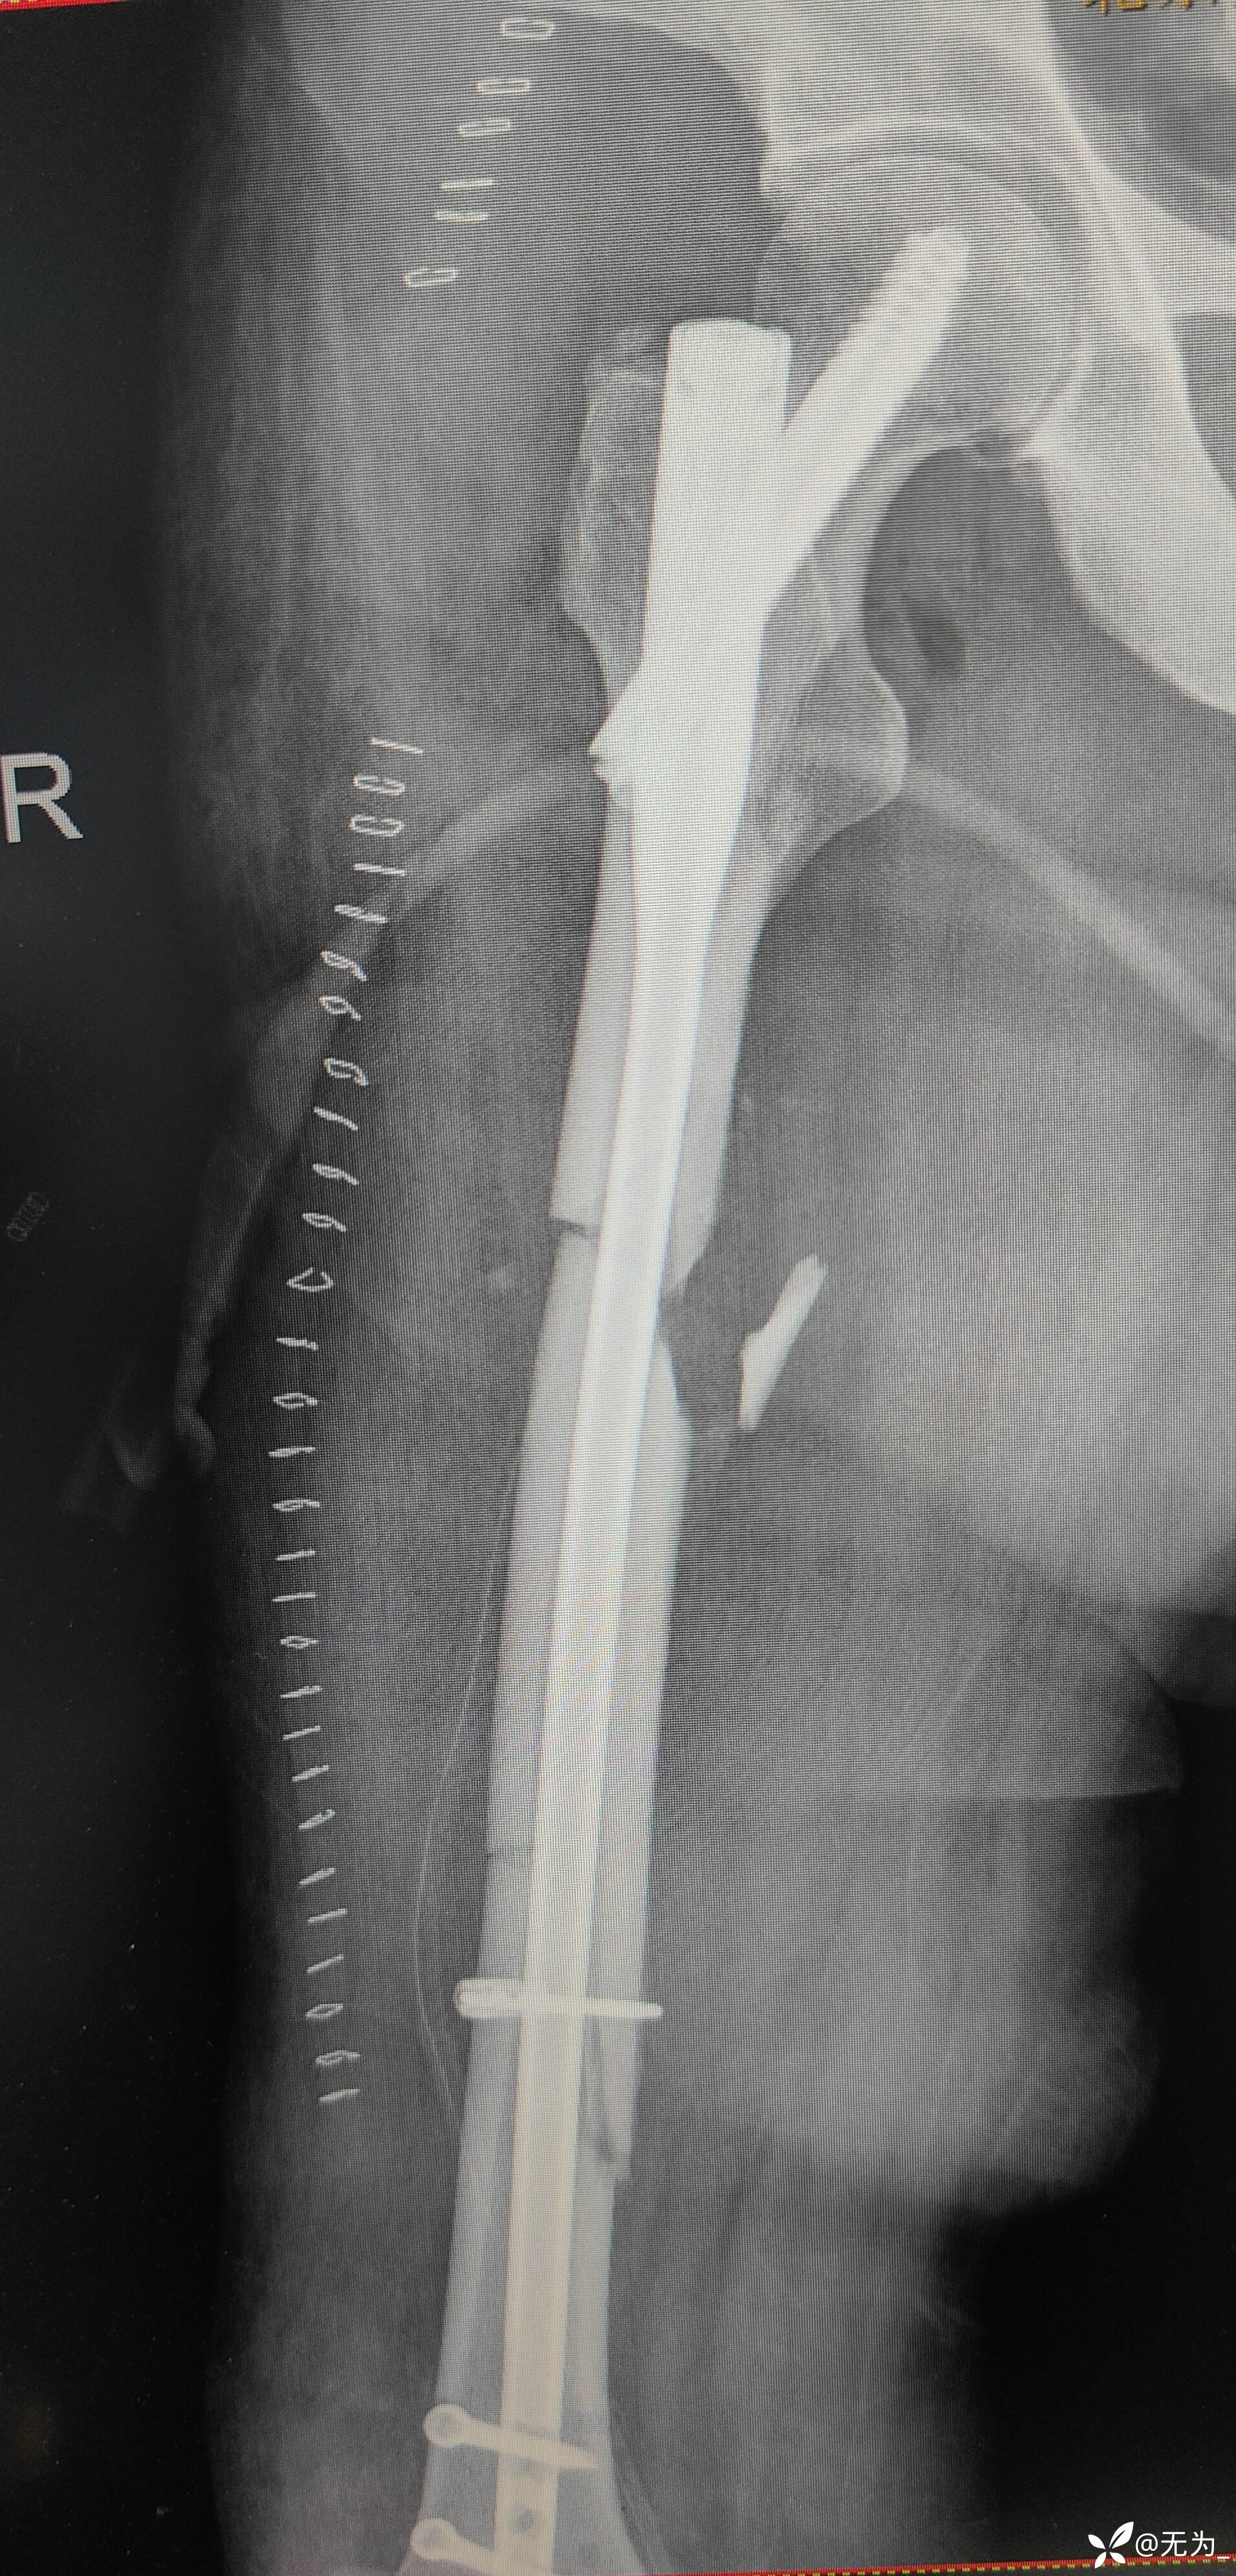

查体:右大腿中段前外侧两公分开放伤口,渗血,可处理游离骨块,大腿畸形、肿胀,足背动脉搏动可查。

补液、输血后行头外伤缝合、大腿外架临时固定,转icu,病情逐渐稳定,3周后行右股骨外架拆除,复位内固定。

三段骨折,复位困难且时间长,患者取侧卧位,取大腿外侧切口,切开以后大量肉芽组织,清理折断,牵引复位,远折断钛揽固定,近折端钳夹复位,开孔、扩髓,置入髓内钉,螺钉固定,内侧骨块未处理伴骨缺损,未植骨避免感染。